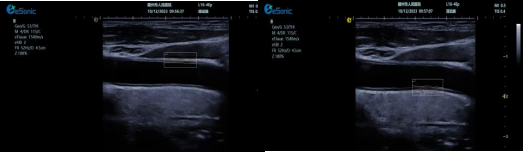

QPWV 彩色脉搏波传导速度定量技术

QPWV 技术是银河官网医疗的极速脉搏波速度测量技术,对脑卒中诊疗优势明显:

image.png

? 可进行动脉壁运动速度 - 时间彩色成像,直接测量单点脉搏波传导速度及相关参数(如 BSES 时的速度及标准差)。

? 能在血管内中膜增厚前的内皮功能不全阶段检测异常,对早期动脉硬化评估极具临床价值。

? 操作简单直接,无需附加设备,影响因素少,检测快速、重复性和稳定性高。